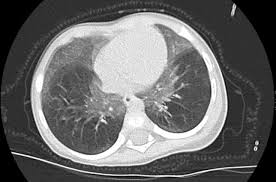

Informes médicos en Salamanca y Madrid, y una imagen de unos pulmones de un paciente con enfermedad pulmonar por hiperplasia de células neuroendocrinas. Fotos cedidas por la familia / Acta Pediátrica Española

Imagen principal - Informes médicos en Salamanca y Madrid, y una imagen de unos pulmones de un paciente con enfermedad pulmonar por hiperplasia de células neuroendocrinas.

Continúan su relato con la primera visita al Hospital Infantil Universitario Niño Jesús en Madrid en noviembre de 2024 donde «nos vieron en neumología del Niño Jesús. Con sólo desnudar al niño el neumólogo dijo 'Aquí pasa algo, esto no es normal' y le pidió un TAC pulmonar, y desde noviembre de 2024 está con oxígeno 24 horas y diagnosticado de la enfermedad pulmonar por hiperplasia de células neuroendocrinas».